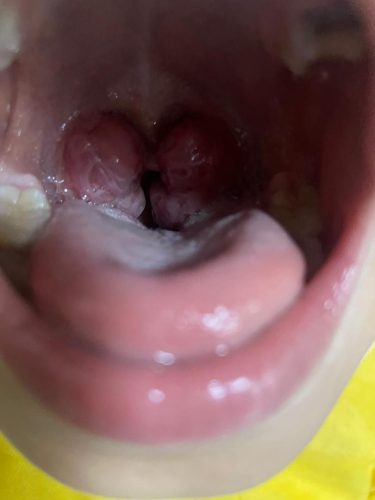

لوزه ها دو بافت کوچک لنفاوی هستند که در قسمت انتهایی حلق و دو طرف گلو قرار دارند. این بافتها بخشی از سیستم ایمنی بدن هستند و نقش مهمی در دفاع از بدن در برابر عفونتها دارند. با این حال در برخی موارد لوزه ها خود ممکن است منبع عفونت و مشکلاتی مانند التهاب و بزرگی شوند که نیاز به جراحی دارند.

- بزرگ شدن غیر طبیعی و غیر قرینه لوزه ها